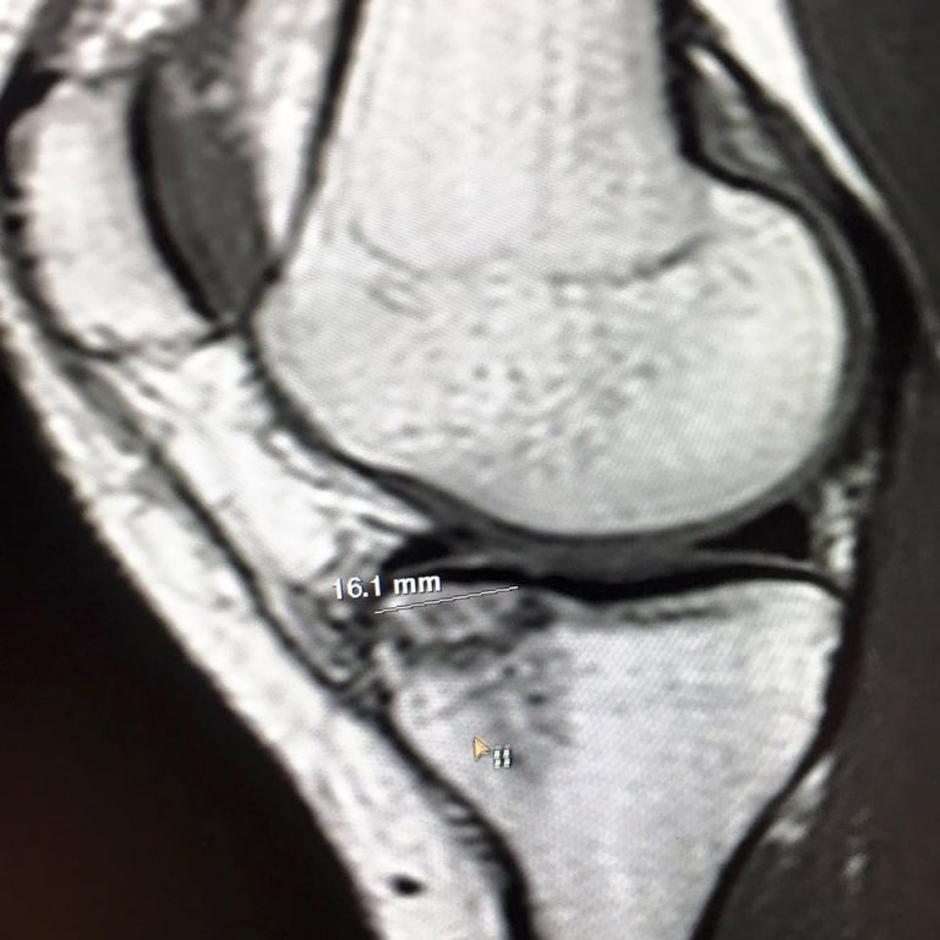

Po prvih informacijah je Vonnova utrpela tanko raztrganino v kolenu, pregled z magnetno resonanco pa je razkril, da je poškodba večja, kot so sprva predvidevali.

''MRI je pokazal precejšen zlom platoja golenice. Vezi izgledajo solidno, kot tudi preostanek kolena. Pogovorila se bom s trenerji in naredila načrt. Obveščala vas bom. Hvala vsem, ki ste mi pomagali prebroditi dan in hvala vsem navijačem za podporo,'' je na družabnem omrežju Facebook zapisala Američanka.

lindsey vonn MRI | Avtor: EPA EPA